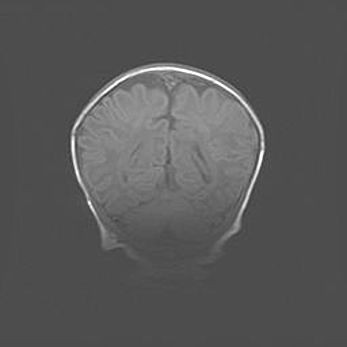

Церебральная ишемия II.

Возраст: 5 дней

Вес: 3400 г

Пол: женский

Окружность головы: 35 см

Срок гестации: 39 недель

Церебральная ишемия – это заболевание, характеризующееся недостаточностью (гипоксией) либо полным прекращением (аноксией) снабжения мозга кислородом по причине закупорки одного или нескольких сосудов. Это приводит к  что метаболическим расстройствам различной степени тяжести в тканях головного мозга, развитию коагуляционных некрозов и гибели нейронов.